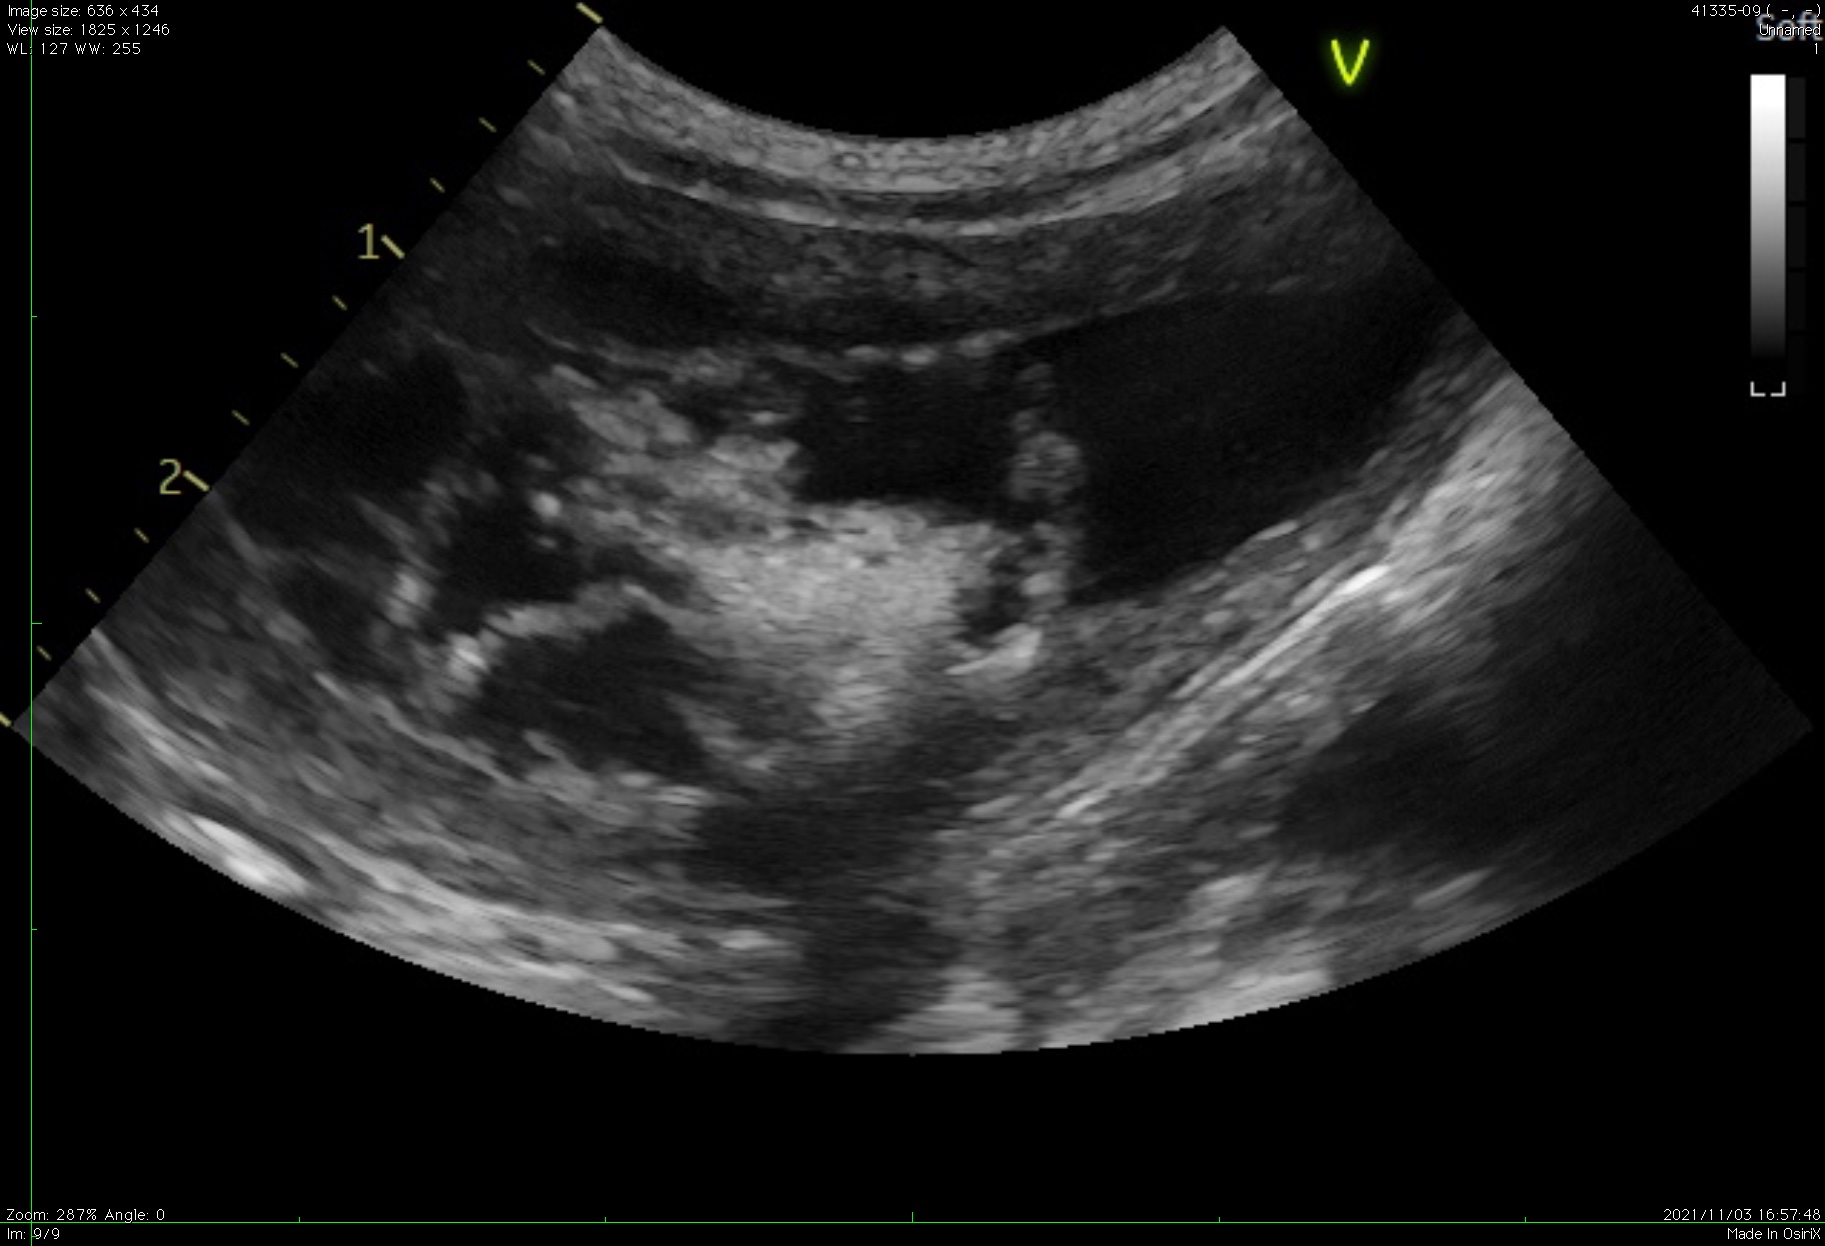

特発性膀胱炎で血餅ができている様子